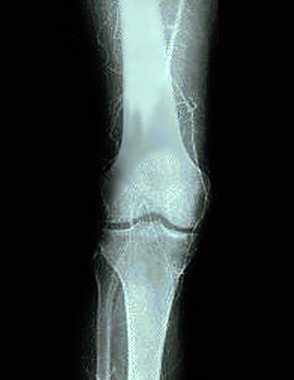

Ангиография

Ангиография.